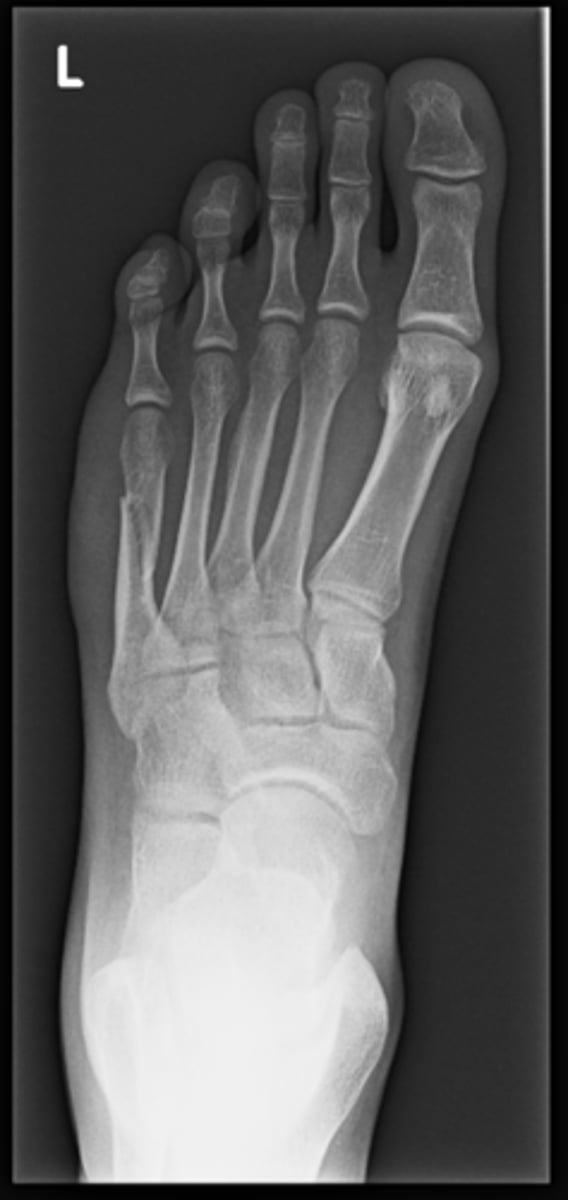

Left AP foot

View?

<p>View?</p>

New cards

Talus

ID 1

92

Medial malleolus

Navicular

ID 3

Medial cuneiform

ID 4

<p>ID 4</p>

Base of 1st metatarsal

ID 5

96

Head of 1st metatarsal

Lateral sesamoid bone

ID 7

98

Medial sesamoid bone

Cuboid

ID 9

100

Base of 5th metatarsal

ID 10

<p>ID 10</p>